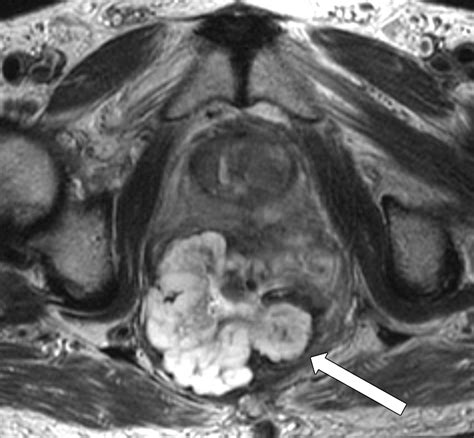

Imaging (MRI/CT) Assesses the extent and spread of the disease.